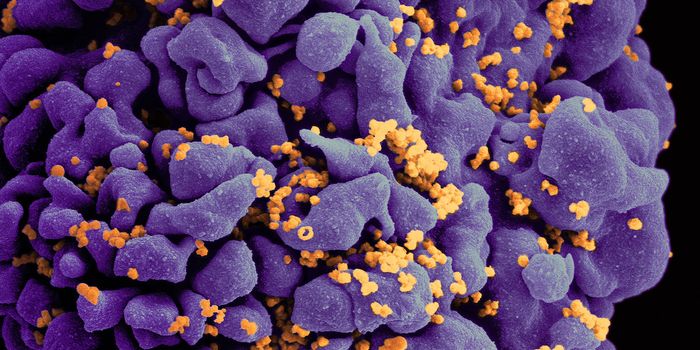

AUG 24, 2020ImmunologyOnce in the body, HIV tracks down T cells that bear the CD4 receptor. It attaches to these immune cells, fusing itself w ...